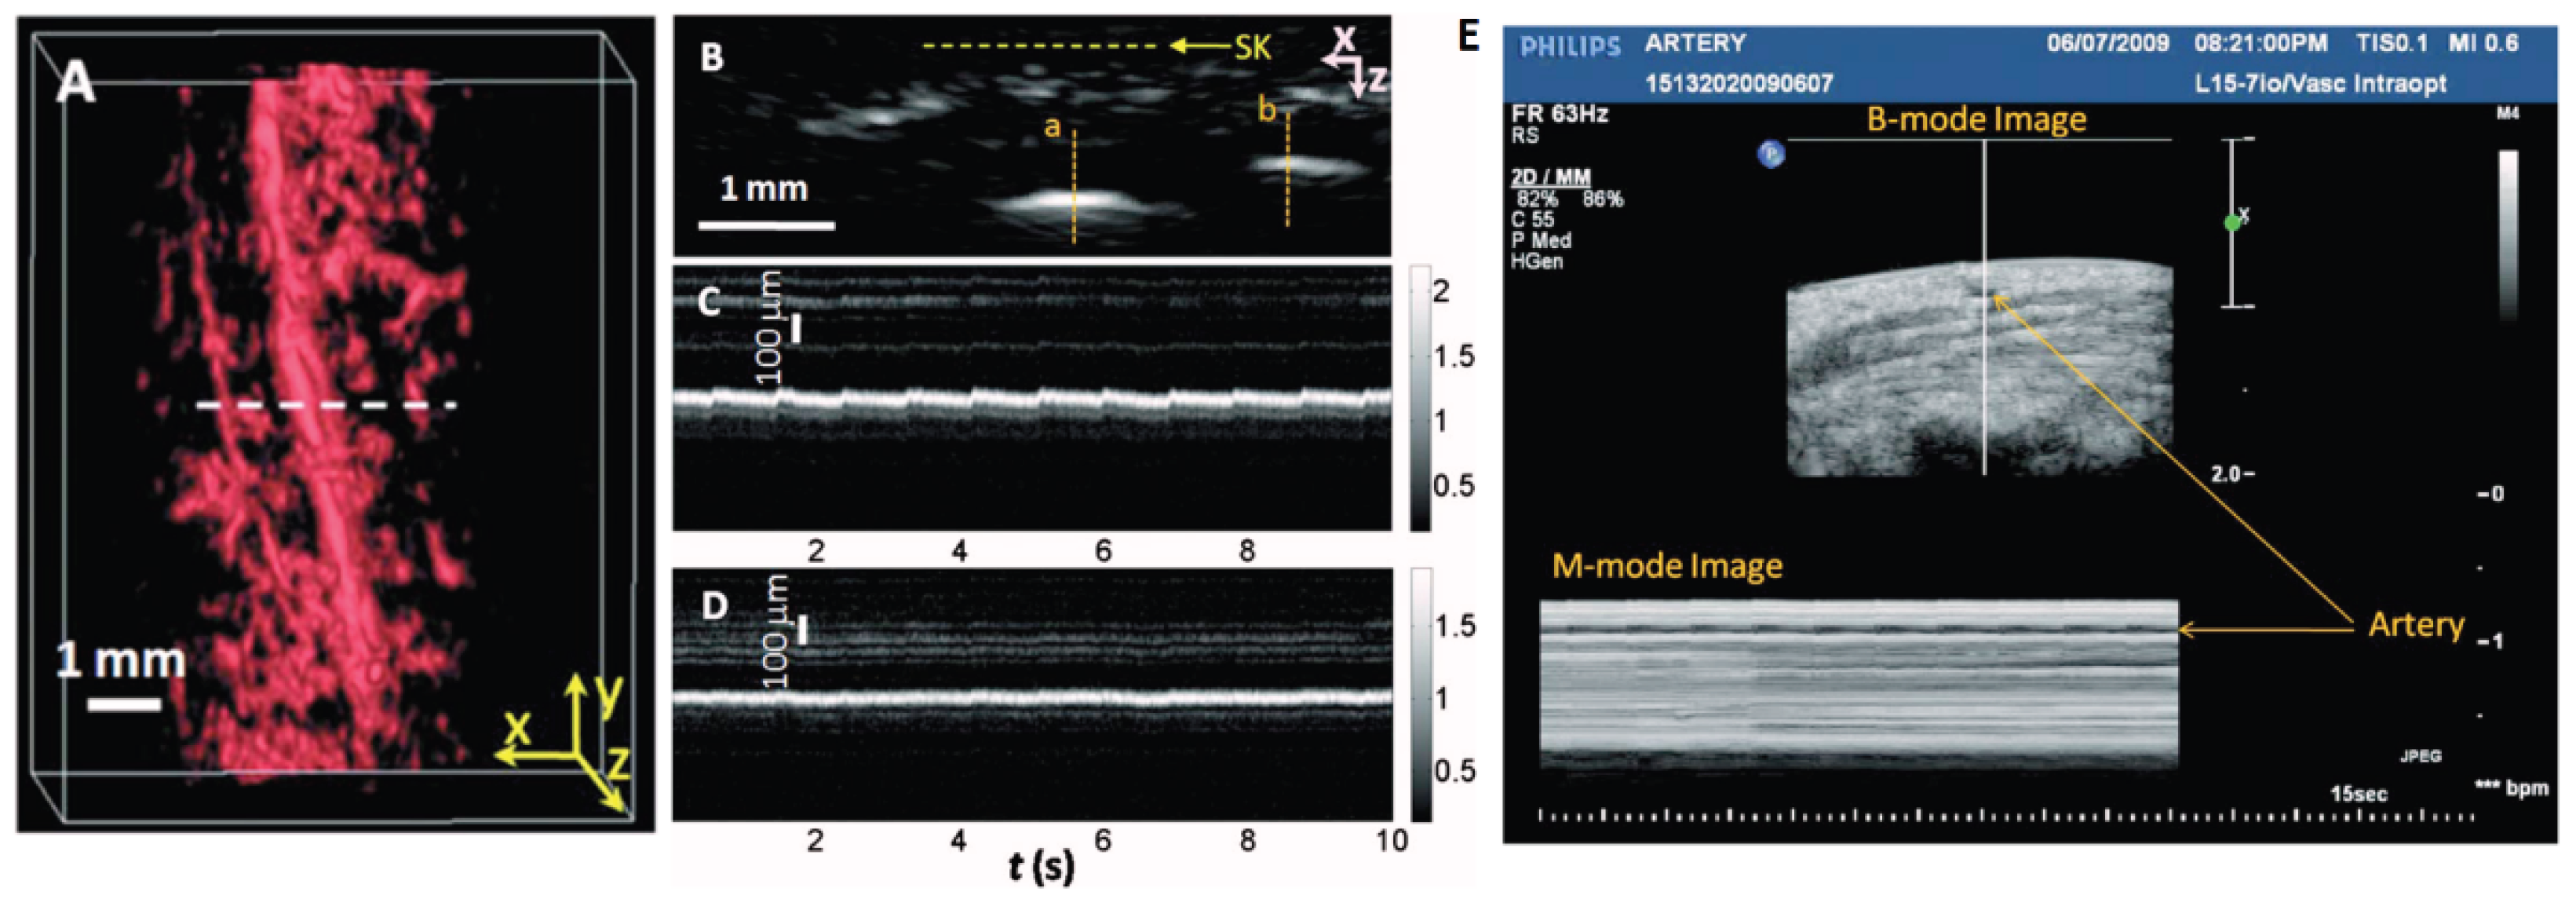

2.1.1. Measurement of Heart Rate Waveform and Vascular Dynamics

- Song, L. , et al., Ultrasound-array-based real-time photoacoustic microscopy of human pulsatile dynamics in vivo. Journal of Biomedical Optics, 2010. 15(2): p. 021303-021303-4. [CrossRef]